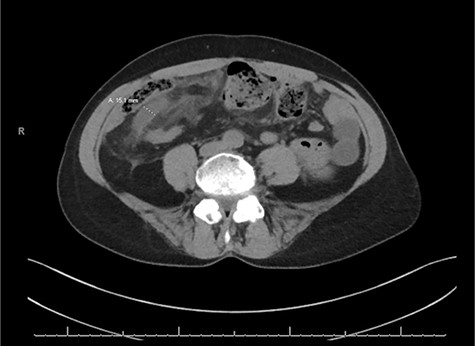

A CT of the abdomen and pelvis without contrast was obtained on admission and revealed a dilated appendix up to 1.5Â cm in size with no evidence of obvious appendicolith (Fig. 1). There was evidence of extensive mesenteric edema in the right lower quadrant of the abdomen. It was felt that these findings were consistent with appendicitis with possible early rupture pattern. Due to her history and likely early ruptured appendicitis, she was felt to be a high surgical risk and she was initially treated on the interval appendicitis pathway. This included IV antibiotic therapy and a repeat CT scan of the abdomen/pelvis 48Â h after initial presentation. She was also placed on a heparin drip and her Coumadin and Plaquenil was held.

Axial slice of the CT of the abdomen/pelvis demonstrating a dilated appendix up to 1.5Â cm in size with mesenteric edema in the right lower quadrant of the abdomen.